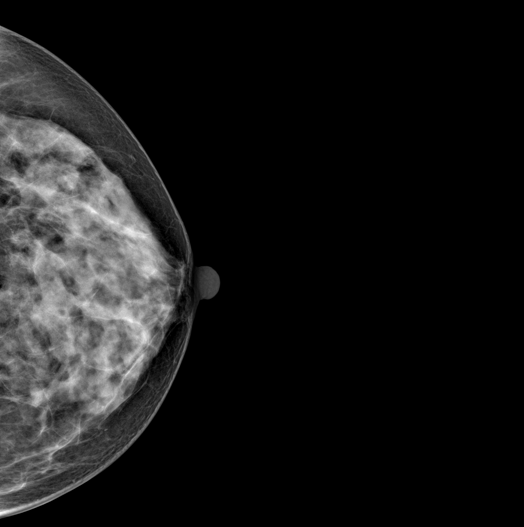

DBT (Digital Breast Tomosynthesis)

The X-ray tube moves on the breast and takes high-definition, high-resolution images with high contrast from various angles.

The images are reconstructed in 3D TO Provide accurate information about the location and condition of the lesion